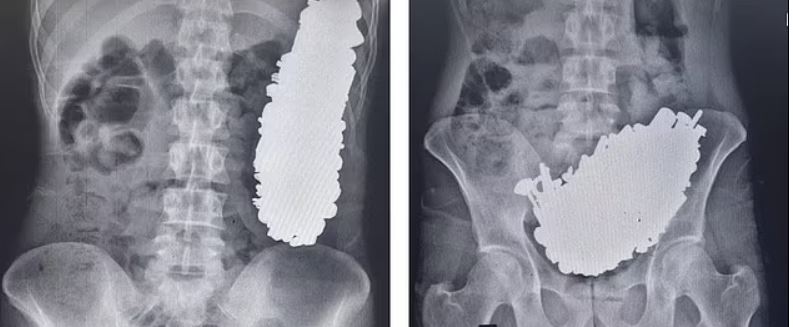

وتظهر الأشعة السينية كتلة المعدن التي كانت تسد مخرج معدة الرجل، ما كان يسبب له آلاماً مزمنة في المعدة وقيءً متكرراً جعله غير قادر على تناول الطعام أو الشراب.

ونقل الأطباء الرجل إلى غرفة العمليات واستخرجوا ما مجموعه 452 "برغي، وجوز، ومفتاح، وحجارة، وأجزاء معدنية أخرى" تزن 2.9 كجم، حوالي 6.5 رطل.